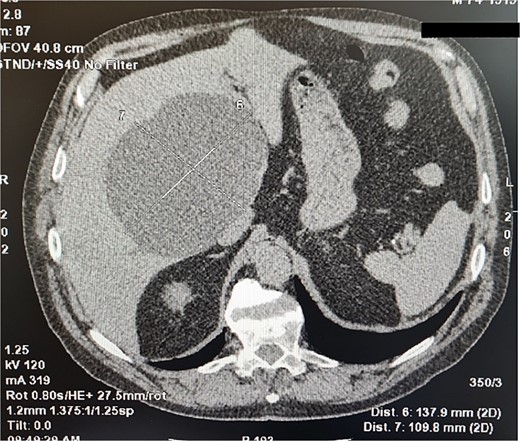

A 75-year-old man was admitted to a surgery clinic after detected a large cystic formation in the right lobe of the liver with prophylactic ultrasound (US) examination. For two years, the cyst was tracked using computed tomography (CT) (Fig. 1) and gradually increased in size from 10 cm to 13 cm. An ELISA method was performed to differentiate from a hydatid cyst, which was positive. Computed tomography described a large cystic formation in the right lobe of the liver involving segments IV, V, VIII measuring 137.9 mm to 109.8 mm with smooth contours. Laboratory findings were normal. A diagnosis of hydatid cyst was made due to the positive ELISA method and the patient was offered laparoscopic surgery.